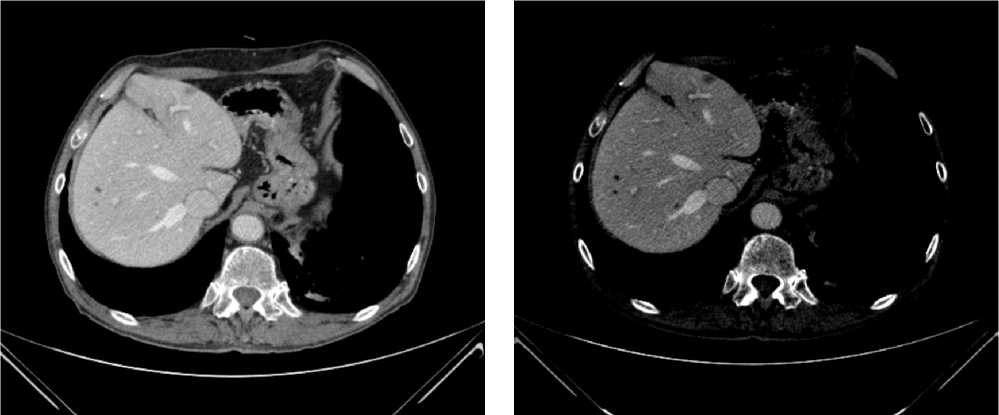

Выполнена компьютерная томография (КТ) органов грудной клетки, брюшной полости в июле 2019 г. Инфильтративных изменений в легких не обнаружено. Выявлено новообразование антрального отдела, малой кривизны и передней стенки желудка, распространяющееся на заднюю стенку, преимущественно на препилорический отдел. Имелись признаки локального перехода образования на большой сальник, гепатодуоденальную связку с периваскулярным ростом и признаками лимфоваскулярной инвазии. Многочисленные забрюшинные ЛУ сливались между собой в конгломераты размерами до 40 × 29 мм с частичным вовлечением почечных артерий. Также билобарно обнаружены немногочисленные очаговые образования в печени до 10 мм. Высказано подозрение на перитонеальный канцероматоз (рис. 3).

Рис. 3. Результаты компьютерной томографии органов брюшной полости у пациента 80 лет с диагнозом метастатический рак желудка с признаками микросателлитной нестабильности (июль 2019 г., до лечения)

Fig. 3. Results of a CT scan of the abdomen in an 80-year-old patient with metastatic MSI-H gastric cancer (July 2019, before treatment)

В результате обследования был установлен диагноз рака антрального отдела желудка (c)T4аN3вM1. По решению онкологического консилиума, учитывающего молекулярно-генетический профиль опухоли, а также возраст пациента, выраженность сопутствующей патологии (в анамнезе острое нарушение мозгового кровообращения (ОНМК), острый инфаркт миокарда (ОИМ), фибрилляция предсердий (ФП), постоянная форма), ограничивающей проведение ПХТ, была начата ИТ 1 линии пембролизумабом. С сентября 2019 г. по декабрь 2021 г. проведено 29 циклов ИТ 1 линии по схеме пембролизумаб в монорежиме с максимальным эффектом частичный регресс (рис. 4). Осложнений лечения не зарегистрировано.